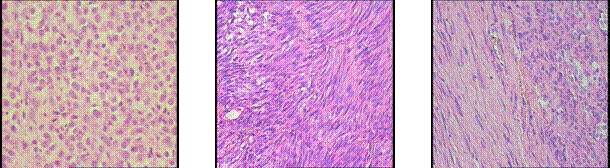

Стромальные опухоли чрезвычайно гетерогенны по морфологии (рис.5). Из 120 стромальных опухолей ЖКТ веретеноклеточный тип строения имели 58,3% опухолей (70/120), 15,0% - эпителиоидно-клеточный (18/120) и смешанный (веретеноклеточный и эпителиоидно-клеточный компоненты) - 26,7% (32/120). Обращает внимание высокая частота встречаемости опухолей со смешанным и эпителиоидно-клеточным типом строения, что, возможно, является особенностью российской популяции (табл.1).

Рисунок 5.

Гистологические варианты стромальных опухолей ЖКТ

(гематоксилин-эозин, х200).

Эпителиодный тип Веретеноклеточный тип Смешанный тип